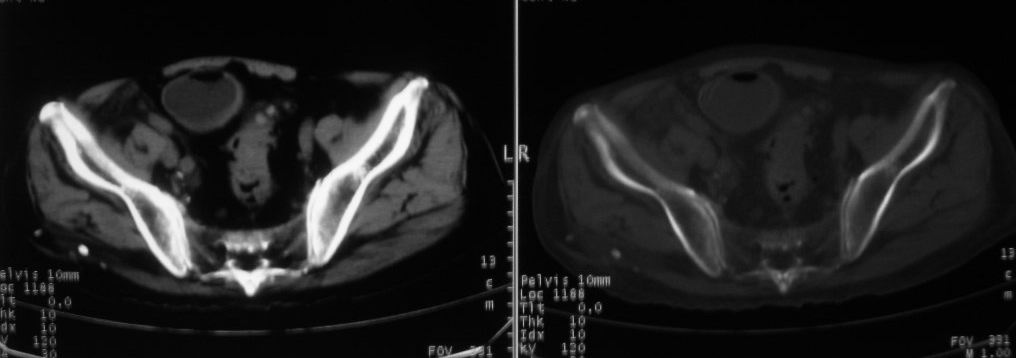

以下是引用深泽交通医院在2008-10-3 15:33:00的发言:[br]前列腺实性增大伴分叶状,与包膜间隙境界不清;椎体松质区间结节样密度影,考虑:前列腺癌,并椎体成骨性转移